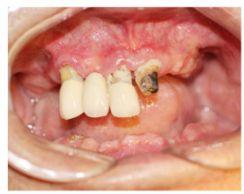

種牙前照片

種牙前X光片